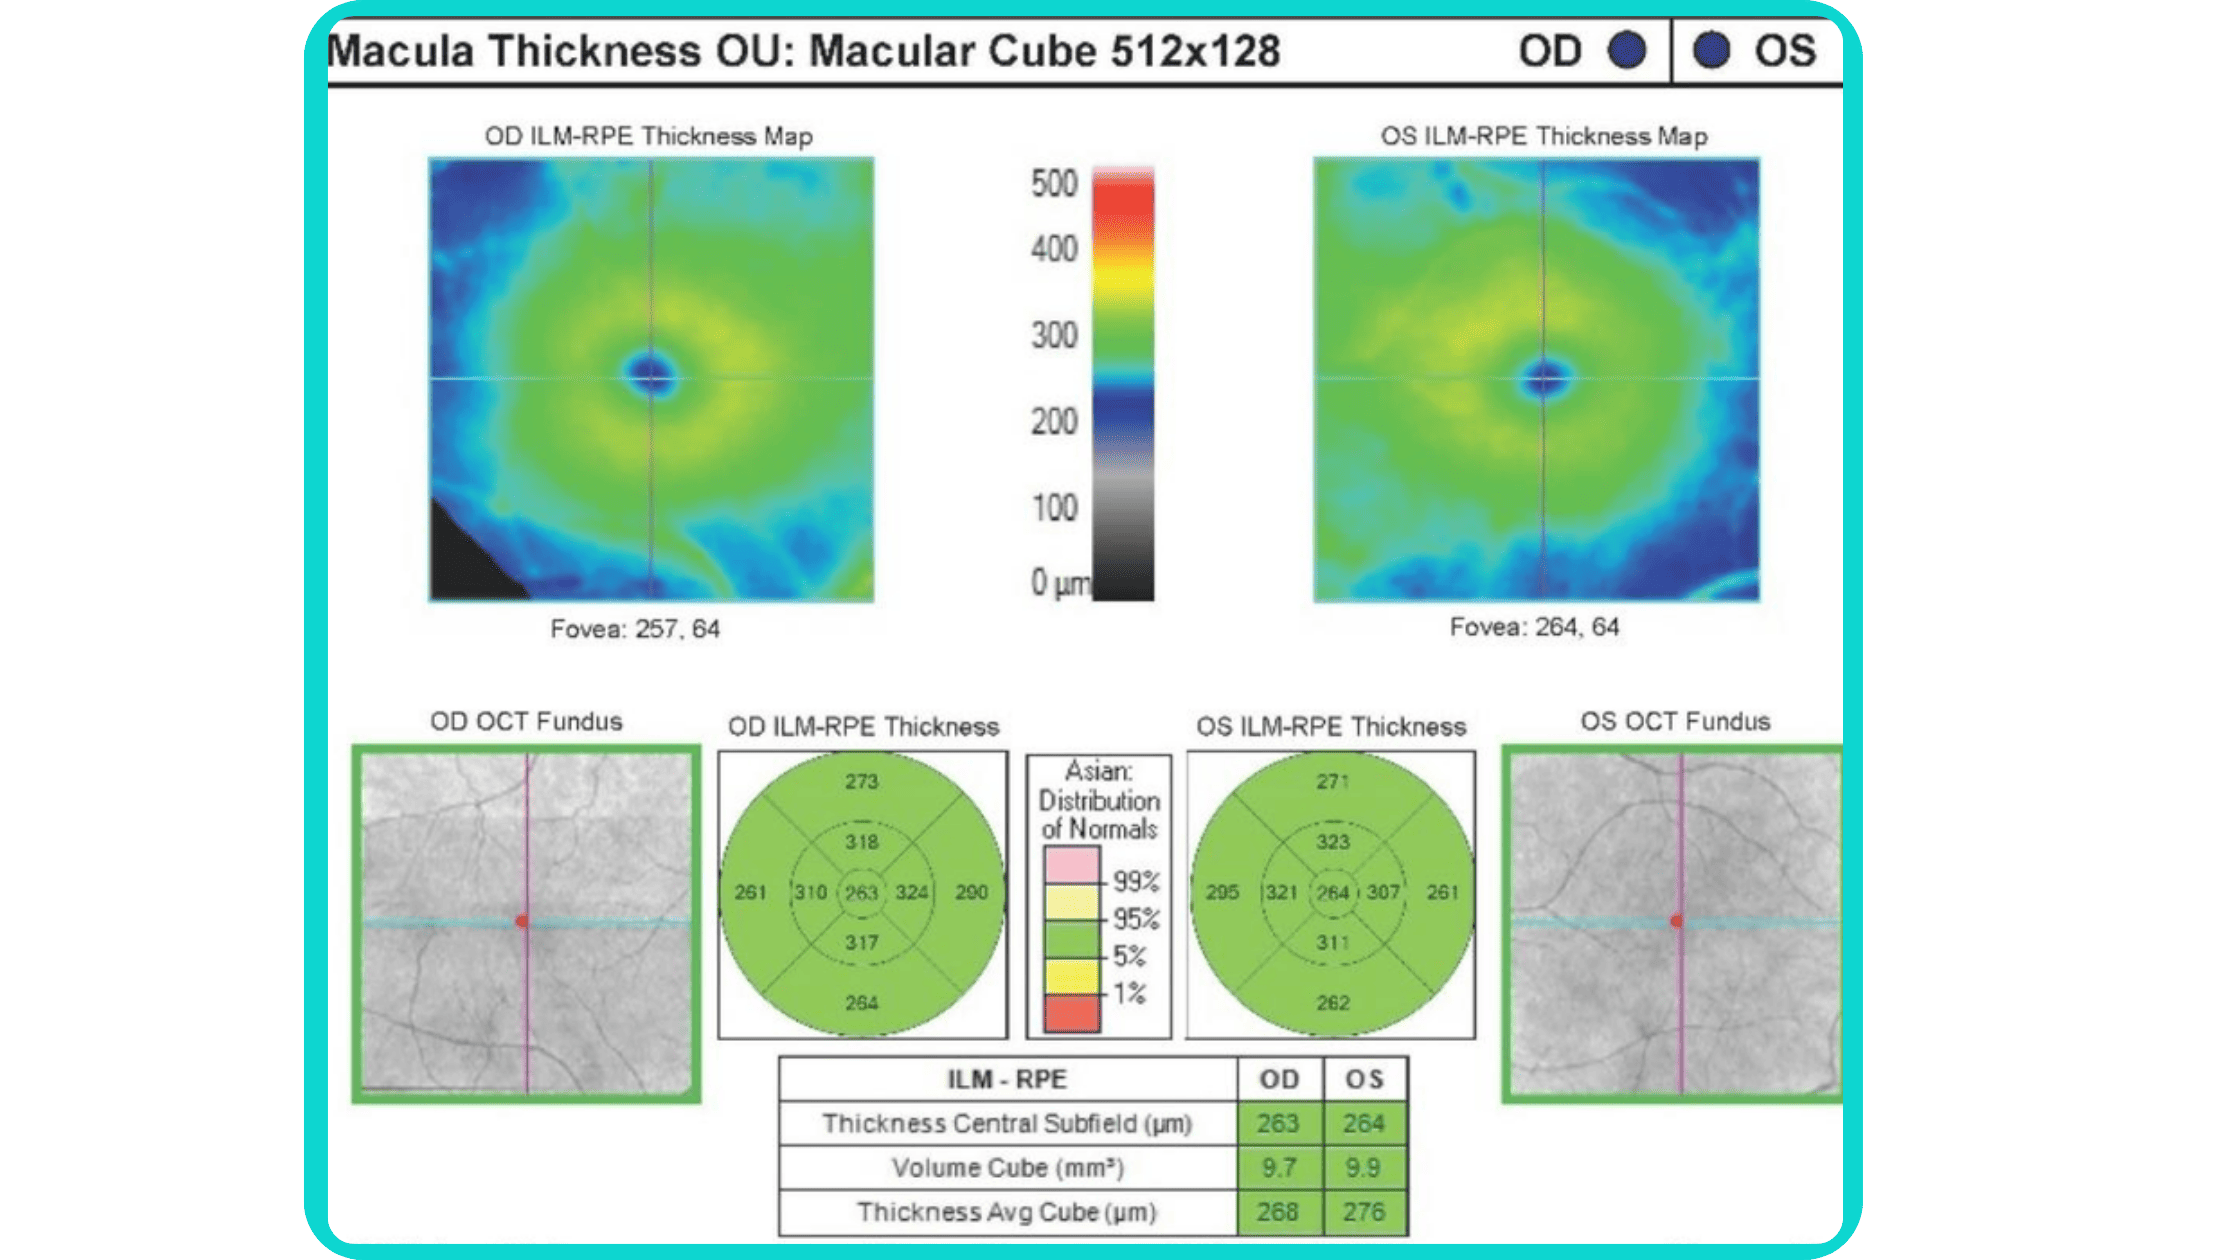

OCT has become a golden standard for diagnosing and monitoring many ocular pathologies, thanks to its unparalleled level of detail in ophthalmic imaging.

While retinal reports vary among OCT models, they typically include:- a foveally centered B-scan,

- a quantitative thickness map,

- and a semi-quantitative thickness map.

The B-scan offers a visual snapshot of foveal architecture and confirms proper scan centering. The quantitative thickness map employs the ETDRS sector map to measure retinal thickness within a 6mm circle around the fovea, with specific measurements for the foveal sector (1mm), inner macular ring (3mm), and outer macular ring (6mm).

Progression analytics enable comparison of serial macular scans, which is invaluable for managing vitreomacular interface disorders and macular edema. The semi-quantitative thickness map provides a broader overview of retinal thickness throughout the scan.

Given this amount of data, it is challenging to identify subtle and localized retinal pathological changes. As a result, entire OCT datasets are represented by few aggregated values, and the standard OCT reports generated by most devices often rely on significant data reduction to simplify interpretation, which you can usually not customize.

In current clinical practice, macular damage assessment typically involves measuring the distance between the ILM and RPE layers, summarized in a post-scan report.

However, these reports often fall short of visualization best practices, employing ineffective or inconsistent color schemes. Additionally, they lack flexibility, with static visuals preventing in-depth examination of specific details. Despite these limitations, these reports remain valuable for many clinicians by distilling complex data into a manageable format.